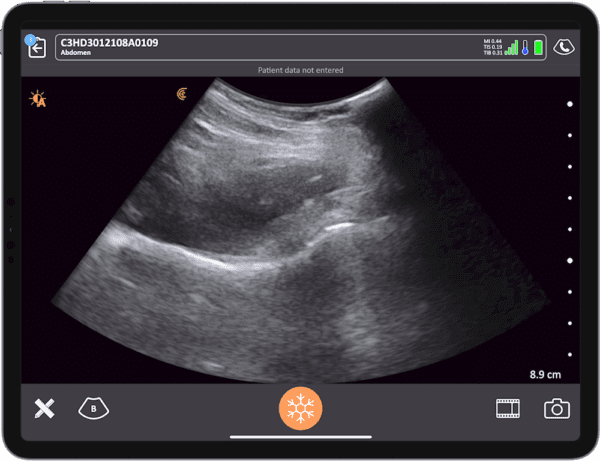

- How to optimize imaging using Clarius high-resolution wireless scanners